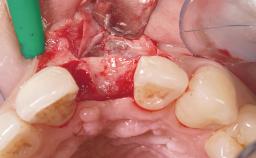

Early Placement of an Implant in a Maxillary Right Central Incisor Site

This 41-year-old female patient was referred to the clinic for the replacement of the right central incisor, since the tooth had developed a root fracture in the long axis that made extraction necessary. The healthy, non-smoking patient was first seen with the tooth still in place. A detailed Esthetic Risk Assessment was performed.The patient was worried about her dental esthetics and had high expectations for a successful treatment outcome from an esthetic point of view. The patient had a medium lip line that displayed parts of the gingiva in the anterior maxilla upon smile.

Placement Protocol Early or late implant placement

Bone Volume Deficient horizontally, allowing simultaneous augumentation